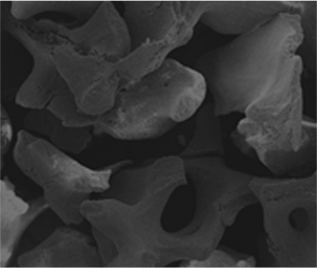

본어스 식립 케이스 10